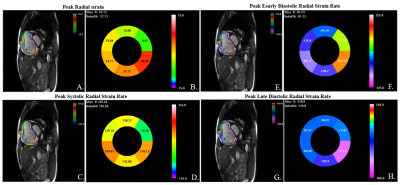

As a sub-cohort from a real-world observation based Chinese national prospective multi-center observational registry study4, newly diagnosed PAH patients were prospectively recruited between January 2011 and December 2017. The designed primary endpoint was any causes of mortality, lung transplantation or atrial septostomy. Each patient was followed by telephone, outpatient or in hospital examinations in a 6-month interval. All enrolled patients received right heart catheterization (RHC) and CMR scanning within one week at the baseline. The hemodynamic criteria for PAH were mean pulmonary arterial pressure (mPAP) ≥ 25 mmHg, pulmonary capillary wedge pressure (PCWP) < 15 mmHg and pulmonary vascular resistance (PVR) > 3 Wood Units measured at rest by RHC. CMR was performed on a 1.5T scanner (MAGNETOM Avanto, Siemens Healthcare, Erlangen, Germany). Breath-hold short-axis cine images encompassing the whole left ventricle (LV) and RV from apex to base were acquired using balanced steady-state free-precession (bSSFP) sequence (repetition time/echo time, 3.2 ms/1.6 ms; temporal resolution, 34 ms; flip angle, 60 degrees; field of view, 280 x 340 mm2; matrix, 150 x 256; voxel size, 1.9mm x 1.3mm; slice thickness, 8 mm). Acquired CMR images were analyzed using a prototype software V2.1 (Trufi Strain, Siemens Healthcare, Princeton, USA). This software uses a deformation registration algorithm to calculate the myocardial strain on a pixel basis, which could be used to analyze the layer-specific strain and strain rate based on cine CMR (DRA-CMR). In this research, RV Peak Strain, Peak Systolic Strain Rate (SSR), Peak Early Diastolic Strain Rate (DSRE), Peak Late Diastolic Strain Rate (DSRL) in the radial, circumferential and longitudinal direction were studied on RV three layers [endocardial wall (ew), middle wall (mw) and epicardial wall (epiw)] and the whole RV myocardium. The representative radial strain and strain rate analysis results were shown in Figure.1.

Figure 1. Right ventricle layer-specific radial strain and strain rate analysis by DRA-CMR.

The Trufi-strain software would track the endocardial and epicardial contours throughout a cardiac cycle automatically and divided the myocardium into three layers. Strain and strain rate values are shown in situ on three layers (A, C, E, G). Strain and strain rate values of six segments are shown in the “Bull’s eye” (B, F, D, H).